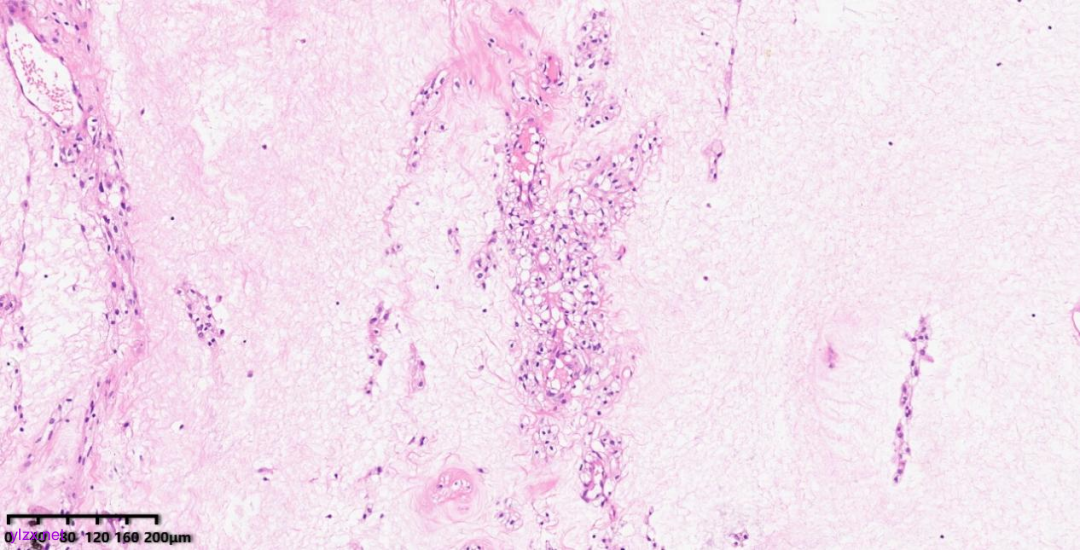

肿瘤细胞以梭形细胞、卵圆形细胞为主,部分为胞浆透亮的上皮样形态,透亮细胞界限较清,胞质淡染或胞浆丰富、嗜酸性,肿瘤内血管丰富,肿瘤细胞围绕血管周围片巢状、束状及放射状排列;肿瘤细胞核异型性不明显,核分裂像少见(<1个/50HPF),染色质开放,可见小核仁;肿瘤间质水肿、黏液变性,纤维胶原增生伴玻璃样变性。

图1~5 低倍镜下:肿瘤细胞以梭形细胞、卵圆形细胞为主,部分为胞浆透亮的上皮样形态,肿瘤细胞分布疏密不均,部分区密集丰富,部分区肿瘤细胞稀少,间质疏松水肿、黏液变性,肿瘤细胞围绕血管周围生长,局部间质纤维胶原增生伴玻璃样变性。